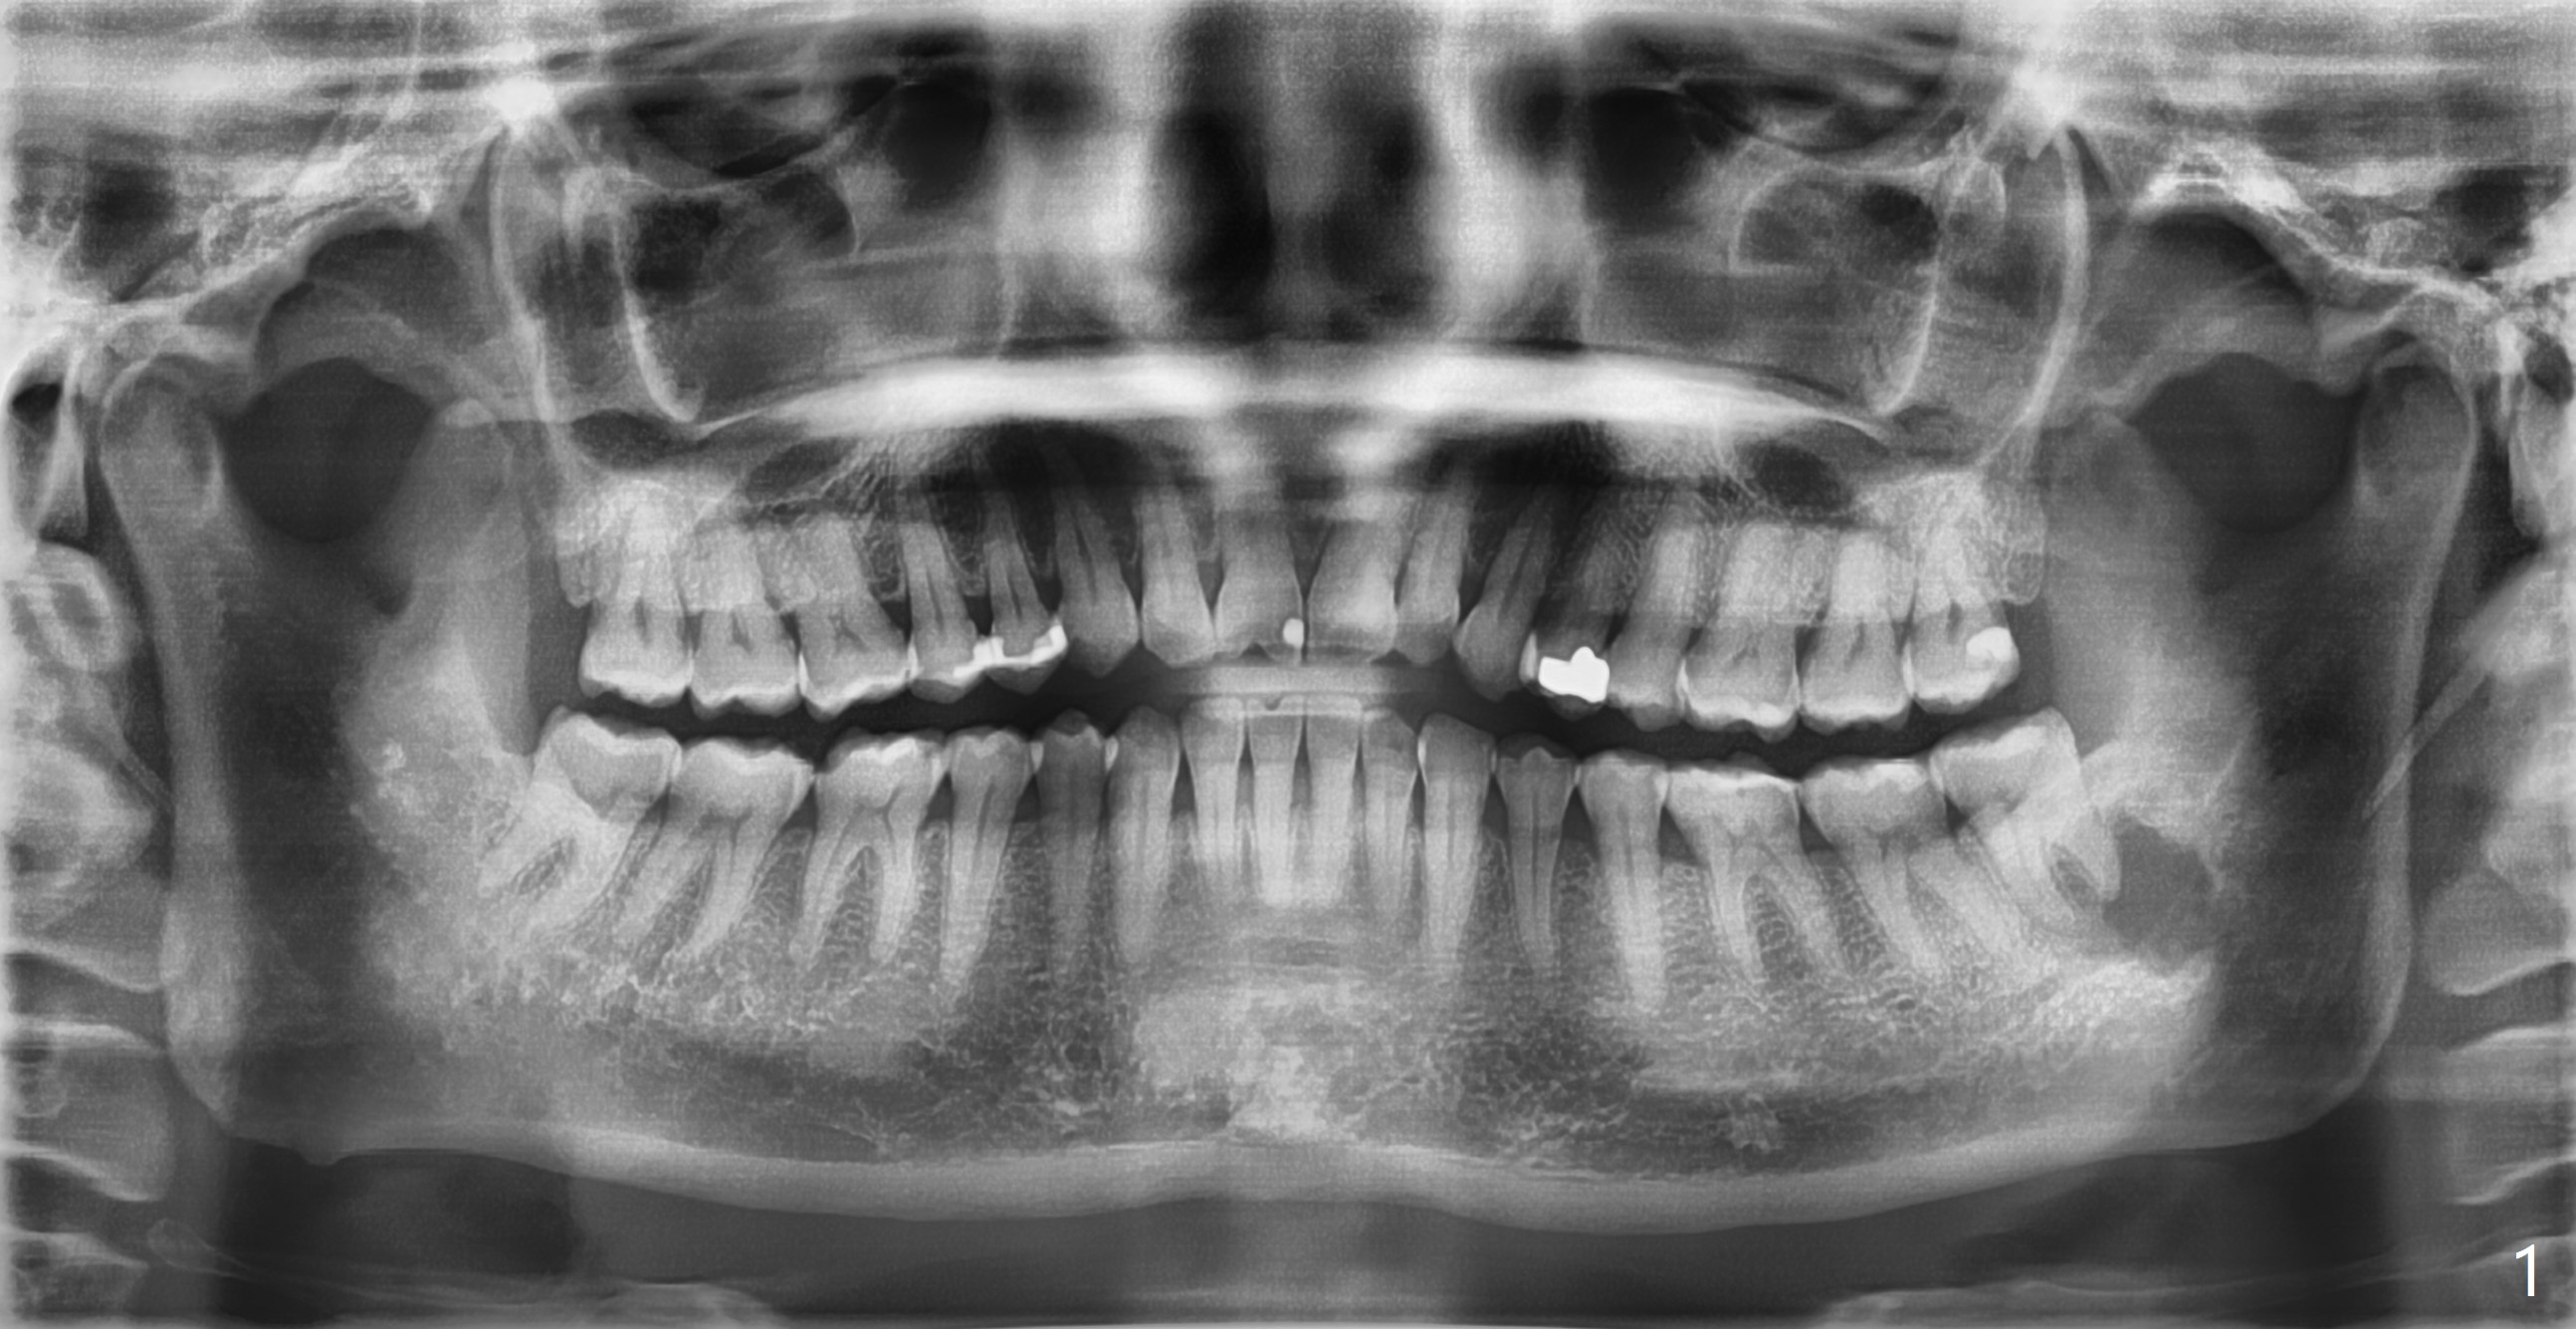

智齿根尖囊肿

51岁女,无症状,可能夜间磨牙,全景片无意发现左下8远中囊肿(图一),牙髓活力测定:活髓,颊侧舌侧无肿胀,牙周袋正常。五年前全景片(图像不清晰)显示病变小。鉴别诊断?她不愿意自费拍摄CT,想用医疗保险诊治,所以转给口外医生。